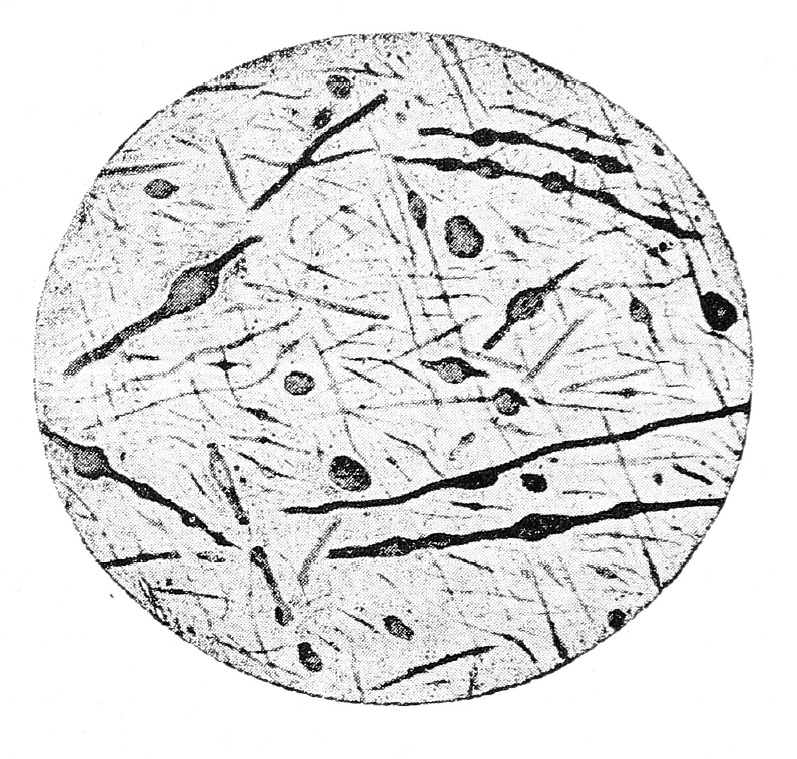

Рис. 1

Окраска по способу Nissl’я. Zeiss. Окул. 2. Объект. 4.

На рисункѣ видны клѣтки съ явленіями хроматолиза; въ нѣкоторыхъ клѣткахъ ядра окрашены значительно интенсивнѣе, чѣмъ протоплазма; видны клѣтки съ вакуолами. Края нѣкоторыхъ клѣтокъ представляются изъѣденными. Нѣкоторыя клѣтки съ сильно сморщенной протоплазмой, ядра въ нихъ совсѣмъ не видны. Окраска большинства клѣтокъ—весьма неравно мѣрна и въ нихъ наблюдается отложеніе глыбокъ. Въ полѣ зрѣнія замѣтно нѣсколько лейкоцитовъ.